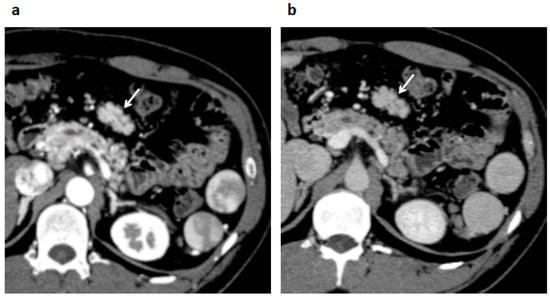

2. Case Presentation